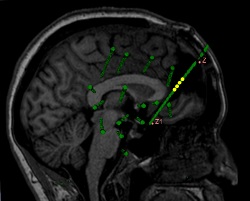

Badanie przedoperacyjne opiera się na identyfikacji ogniska padaczkowego (ang. epileptogenetic zone, EZ), czyli obszaru mózgu, który należy usunąć, aby u pacjenta nie występowały już napady. Do momentu badań przeprowadzonych w ramach projektu EPINET, istniały znaczące ograniczenia w identyfikacji funkcjonalnych markerów pozwalających na jednoznaczną identyfikację EZ. Naukowcy pracujący w projekcie EPINET opracowali półautomatyczną strategię analizy zapisów z elektroencefalografii śródczaszkowej (iEEG) oraz magnetoencefalografii (MEG) u pacjentów z epilepsją. Tym aspektem badań zajmowała się dr Lucia Quitadamo, doświadczona badaczka programu Marie Sklodowska-Curie, która przełożyła te wyniki na powszechnie dostępne oprogramowanie EPINETLAB. Na podstawie analizy wykrytych wahań pola o wysokiej częstotliwości (ang. high-frequency field oscillations, HFO) oraz ich kwantyfikacji w różnych rejonach mózgu, program ten potrafi określić występowanie obszaru związanego z atakami. Oprogramowanie to posiada pełną dokumentację i jest przyjazne użytkownikowi. W trakcie ataku padaczkowego oraz w stanie spoczynku analizuje ono elektromagnetyczny sygnał mózgu pod względem częstotliwości i charakterystyk czasoprzestrzennych. „Jako takie, oprogramowanie to może wspierać praktyków klinicznych w pracach przedoperacyjnych, kiedy to dokonują oni identyfikacji obszaru mózgu, który musi zostać usunięty u pacjentów dotkniętych padaczką niepodatną na leczenie lub lekooporną”, mówi koordynator projektu, prof. Stefano Seri z Uniwersytetu w Aston. Projektowanie oprogramowania – podejście dwukierunkowe Innym celem projektu była walidacja oprogramowania z użyciem danych z analiz inwazyjnych i nieinwazyjnych (odpowiednio: iEEG i MEG). Łączna analiza obu sygnałów umożliwiła solidną walidację algorytmów zaangażowanych w proces oceny. iEEG – metoda inwazyjna wymagana często do określenia źródła aktywności padaczkowej przed operacją – umożliwiła sprawdzenie zachowania mózgu przy zaburzeniach pola o wysokiej częstotliwości, poprzez wprowadzenie markera ogniska padaczkowego. „iEEG stosowane jest często, gdy nieinwazyjne metody diagnostyczne, takie jak EEG wykonywane przez skórę głowy, nie dają jasnych wyników odnośnie położenia ogniska padaczkowego”, wyjaśnia prof. Seri. Mając na względzie użytkowników niedoświadczonych, system EPINETLAB został całkowicie zintegrowany z platformą EEGLAB(odnośnik otworzy się w nowym oknie), która jest przez neuronaukowców powszechnie wykorzystywana w analizie zapisów elektromagnetycznych mózgu. Technicy nie muszą mieć zaawansowanej wiedzy o programowaniu i mogą w prosty sposób używać tego oprogramowania, na potrzeby korzystania z funkcjonalności platformy EEGLAB oraz bardziej specyficznych funkcji systemu EPINETLAB. Nieustanne zbieranie danych „Wyjściowo, baza składała się z danych iEEG 60 pacjentów, pobranych przez trzy różne europejskie centra”, nakreśla prof. Seri. Zebranie tych danych było efektem transnarodowej współpracy szpitali Niguarda i Bambino Gesu z Włoch oraz szpitala Women's and Children's Hospital z Birmingham w Zjednoczonym Królestwie. Co więcej, od 13 pacjentów pediatrycznych objętych opieką operacyjnego leczenia padaczki szpitala dziecięcego w Birmingham pobrane zostały dane z badania MEG w ramach oceny przedoperacyjnej na Uniwersytecie w Aston. Informacje te umożliwiły wdrożenie i ostateczną walidację systemu EPINETLAB w okresie trwania projektu. „Walidacja nadal trwa. Zbieramy duży zestaw danych z międzynarodowych centrów leczenia padaczki i dodajemy nowe funkcje do oprogramowania EPINETLAB, gdyż mamy świadomość, że użytkownicy ich potrzebują”, kontynuuje prof. Seri. Przyszłość systemu EPINETLAB Dzięki publikacji w International Journal of Neural Systems, wysoce cenionego czasopisma naukowego, oraz rozpowszechniania informacji podczas International Epilepsy Conference odbywającego się we wrześniu 2017 r. w Barcelonie, oprogramowanie EPINET zaistniało na arenie międzynarodowej. Prof. Seri wskazuje, że „badania w ramach projektu EPINET umożliwiły nawiązanie współpracy z instytucjami międzynarodowymi mającymi na celu wykorzystanie wypracowanego w toku projektu know-how oraz poszerzenie wiedzy o kwestiach związanych z epilepsją”. Współpraca z partnerem przemysłowym, firmą Micromed S.p.A. światowym liderem w produkcji systemów wykorzystywanych w neurofizjologii, przetarła szlaki dla poprawy współpracy środowiska naukowego z przemysłem. Wspólnie, partnerzy zbadali możliwość zintegrowania wdrożonych narzędzi do ich pakietów oprogramowania diagnostycznego. Współpraca ta pozwoli na umocnienie Europy jako lidera na tym polu, co jest dla UE celem strategicznym. Prof. Seri tak podsumowuje znaczenie badań przeprowadzonych w ramach projektu dla jakości życia pacjentów z epilepsją, która jest ściśle związana ze stopniem ograniczenia napadów padaczkowych po operacji: „EPINET dostarczył w tej dziedzinie badań nad fenotypem wolnym od napadów oraz nieocenione środki dla poprawy identyfikacji obszaru odpowiedzialnego za generowanie ich”.